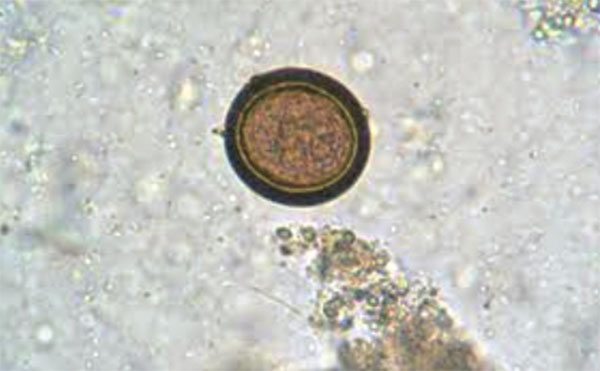

Por otro lado, el estadio larvario de Tae-nia solium -luego de la ingestión accidental de sus huevos por parte del ser humano- formará los cisticercos en diversos tejidos y órganos, distribuidos mediante el torrente circulatorio, produciendo así la cisticerco-sis. Tras esta breve explicación, ahora se mencionan los rasgos más distintivos de cada enfermedad.

• La enfermedad se adquiere al ingerir hue-vos de Taenia solium en alimentos conta-minados con materia fecal huma-na.

• El hombre se comporta en este caso, como huésped intermediario de Taenia so-lium, pues acoge cisticercos (larvas en-quistadas) en sus tejidos y mayormente en órganos como el ojo y el cerebro.